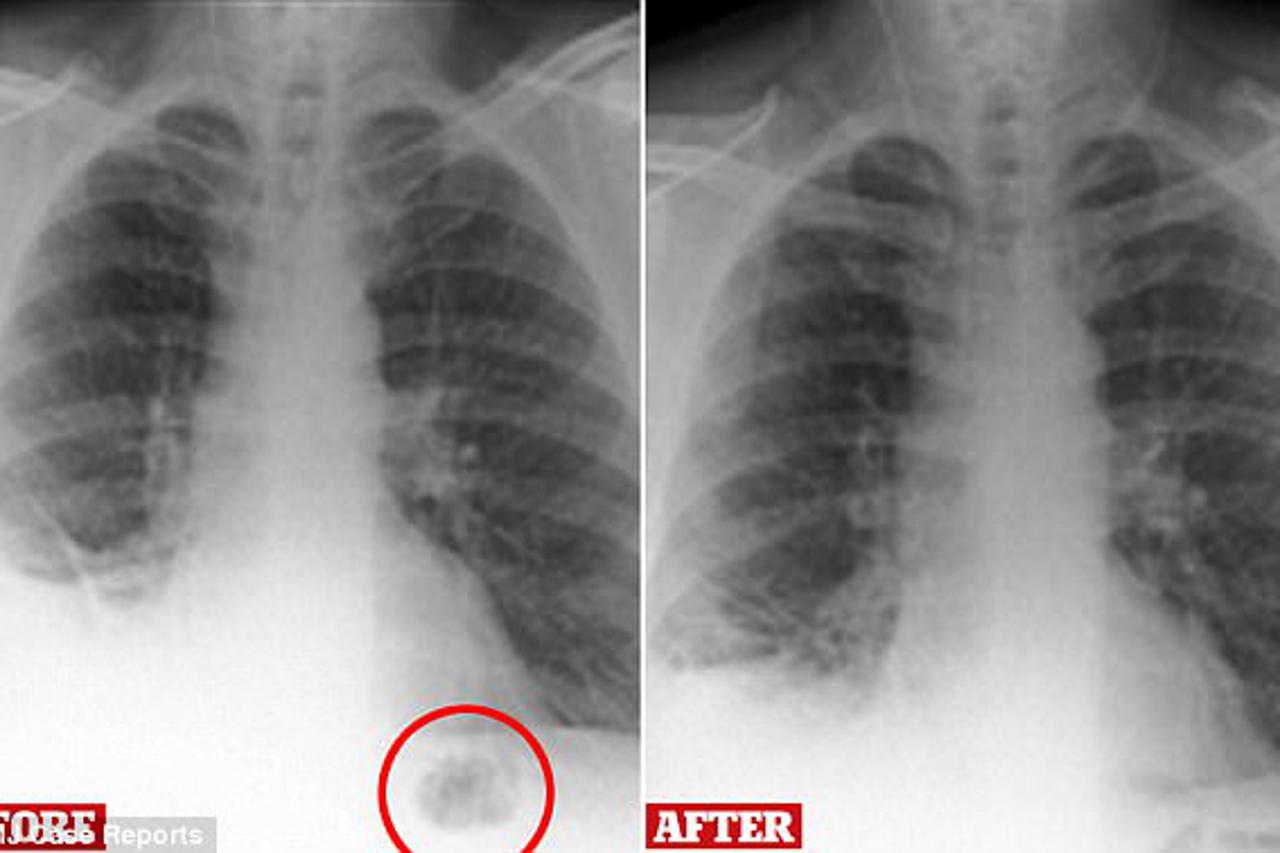

Muškarac (47) liječnike je posjetio nakon jakog kašnja, a rengden je otkrio crnu mrlju na njegovim plućima